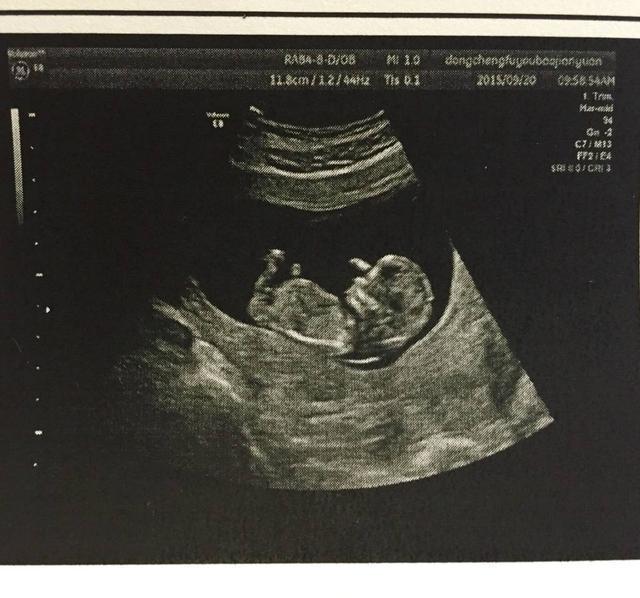

快到4个月的时候,去做B超产检,医生的一句话更让她们惊喜万分——双胞胎。但是随后一句话,让她承受不了,医生说有可能是连体婴儿。后面她根本没听到医生说些什么,就这样,她走出了B超室,在老公的陪伴下回家了。整天一泪洗面,想着各种结果,都不敢面对。

医生也建议在这种情况下做引产手术。可是这位妈妈觉得孩子无辜的,感觉着胎动越来越明显,也越来越频繁,这位妈妈更舍不得了。当即做了个决定,她要把这两个孩子生下来。时间一天一天的过去,全家人也都一天一天的紧张,心情越是到后面越是更加复杂,生下来不知道如何面对。可以怕终究要到见面的那一天,就这样带着复杂的心情,给推了产室,进行了分娩。就在孩子分娩后的那瞬间,当然所有人惊呆了,两个孩子完好,根本没有发现连体的情况。医生直呼,幸运,太让人意外了。老公和家人听到这个消息后,眼泪全出来了!这可能是最好的结果了。医生最终的结论,两个婴儿由于子宫太小了,婴儿挤在一起,相互抱着,B超根本看不出来,所以感觉像是连体的。